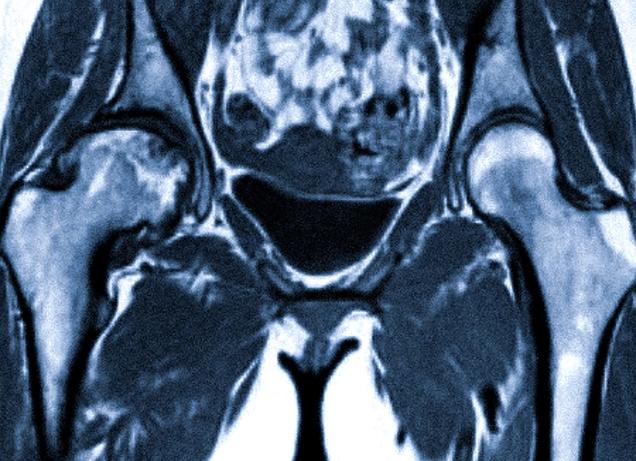

МРТ костей таза

МРТ или компьютерная томография костей таза представляет собой современный лучевой неинвазивный метод исследования организма. Данная методика позволяет исследовать кости и ткани таза. Действие томографа основывается на физических свойствах ядерного магнитного резонанса.

Исследуемый участок тела выступает источником радиосигнала. МРТ улавливает хаотичные сигналы, которые в свою очередь обрабатываются специальным компьютерным оборудованием. Компьютер преобразовывает сигналы в томограмму. Снимок указывает на наличие или отсутствие того или иного патологического процесса в костях таза. Расшифровкой результатов МРТ занимается профессиональный специалист, имеющий соответствующую квалификацию.

Компьютерная томография показывает наличие определенных патологических процессов в тазовых костях. Это защемление нервных окончаний, сухожилий, переломы костей. Доброкачественные или злокачественные опухоли не только в костях таза, но и в окружающих мягких тканях, уровень распространения и прорастания опухоли в ткани. На томограмме можно увидеть степень метастазирования из других органов, например при раке предстательной железы, дисплазию костей, аномалии развития костной ткани, патологические процессы в тазобедренных суставах, наличие инородных тел в тканях, степень деструкции костей при стандартном течении болезни Крона.

МРТ диагностика позволят получать четкие снимки костей таза, благодаря которым врач может определить, какой патологический процесс присутствует в анамнезе пациента. Исследование тазового дна, подвздошных, лобковых, седалищных костей, тазобедренных сочленений, илеосакральных суставов дает полную картину состояния больного.

Магнитно-резонансная томография (МРТ) костей таза позволяет визуализировать не только костные структуры, но и мягкие ткани, поэтому обладает высокой диагностической ценностью. Используемый принцип ядерного магнитного резонанса более безопасен для организма человека, чем рентгеновское излучение. При этом детализация изображений значительно выше, чем на компьютерной томограмме или обычном снимке, поэтому часто врачи рекомендуют сразу сделать МРТ костей таза, не тратя время на другие методы диагностики.

Что показывает МРТ костей таза? При помощи МРТ можно получить изображение костей таза, илео-сакральных и тазобедренных сочленений, мягких тканей. Данный метод очень информативен при сложных травмах, так как позволяет получить точную картину повреждения и спланировать оперативное вмешательство. Часто назначают МРТ при болезненных ощущениях в области таза, нарушениях движений в суставах. С помощью данного метода выявляются воспалительные (сакроилеит, коксит) и дегенеративные процессы, новообразования, деформации (врожденные и приобретенные).